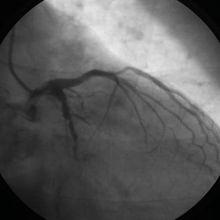

左前分支傳導阻滯(圖)前壁心肌梗死如果您有上述情況,我們平時要多注意休息,切忌動怒,忌菸酒,經常複查心電圖,尤其是有胸悶這些症狀時,發現問題即時處理。另一方面我們也應當保持樂觀的態度。1,單純心電圖存在左前分支傳導阻滯,不會引起任何臨床症狀,更不會有什麼危險!2,引起左前分支傳導阻滯的原因很多,例如風心病,先心病,心肌病,心肌炎,冠心病,高心病等器質性心臟病都可以引起。但臨床上也有很多查不出原因的!好多年輕人正常體檢,也常見左前分支傳導阻滯,原因不明,可能是先天發育所致。3,如果是器質性心臟病引起,主要治療原發病。如果不明原因,就不需要任何治療!4,因此,你可做心臟彩超等檢查,排除器質性心臟病的可能。排除後就不用擔心了。 另外如果有心肌缺血、前壁心肌梗死等情況發生,需要治療臨床採用倍他樂克,心血康,洗血王重組水蛭素來進行治療,也可以用心腦至寶等保健品來進行預防。